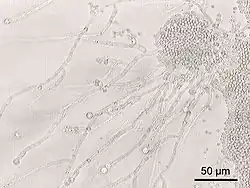

Fungi also make up a part of the gut flora, but less is known about their activities.[42]

Due to the prevalence of fungi in the natural environment, determining which genera and species are permanent members of the gut mycobiome is difficult.[43][44] Research is underway as to whether Penicillium is a permanent or transient member of the gut flora, obtained from dietary sources such as cheese, though several species in the genus are known to survive at temperatures around 37 °C, about the same as the core body temperature.[44] Saccharomyces cerevisiae, brewer's yeast, is known to reach the intestines after being ingested and can be responsible for the condition auto-brewery syndrome in cases where it is overabundant,[44][45][46] while Candida albicans is likely a permanent member, and is believed to be acquired at birth through vertical transmission.[47]